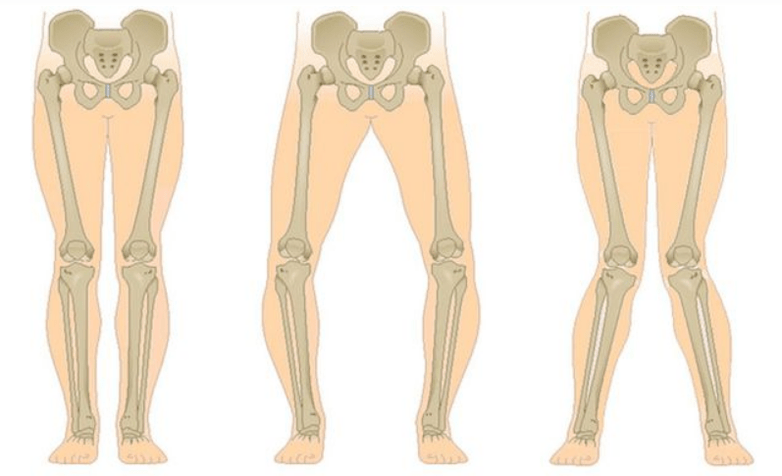

The last stage of gonarthrosis is distinguished by the fact that the pain becomes almost constant, causing anxiety not only when walking, but also at rest and even at night, when patients have to look for a comfortable position for sleeping.Movement is more limited: it is difficult to bend and straighten the leg completely.The joint deforms and increases in volume.Valgus (X-shaped) or varus (O-shaped) deformities of the legs are often observed.The gait becomes unstable and sways.In more serious cases, a cane or crutches are required.

With arthrosis (osteoarthrosis), in addition to the progressive destruction of cartilage, the loss of its elasticity and shock-absorbing properties, bones are gradually involved in the process.Under load, sharp edges (exostoses) appear, which are mistakenly considered "salt deposits" - in classic arthrosis no salt deposits occur.As osteoarthritis progresses, it continues to “eat” the cartilage.Then the bone is deformed, cysts form there, all structures of the joint are affected and the leg bends.

Depending on the number of joints affected, a distinction is made between unilateral and bilateral gonarthrosis.